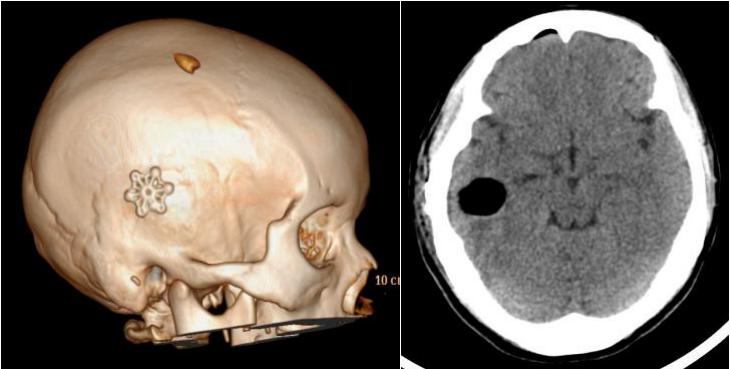

术后CT见:病变完全切除,骨孔仅一枚连接片即可完全覆盖

随着神经内镜技术的发展,对于包括海绵状血管瘤在内的许多疾病,亦可以通过微创的方法进行治疗。该病例采用的微骨孔“burr hole”技术,手术只需小面积剃头,术中骨孔仅需一梅花连接片即可完全覆盖,不影响患者美观的同时,还能更大程度地减少创伤,有利于患者康复,早日回归正常工作、生活。